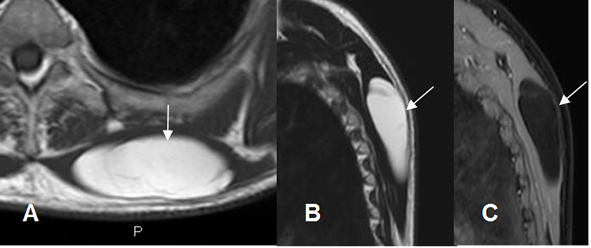

Fig 166 C. Liposarcoma bien diferenciado.

A: RM coronal en T1 y B: RM coronal en T2. Imagen ovalada y de bordes bien definidos en la parte medial del muslo, que sigue la señal de la grasa.

C: RM coronal en STIR No hay completa supresión de la señal en esta secuencia y corresponde a un liposarcoma bien diferenciado.